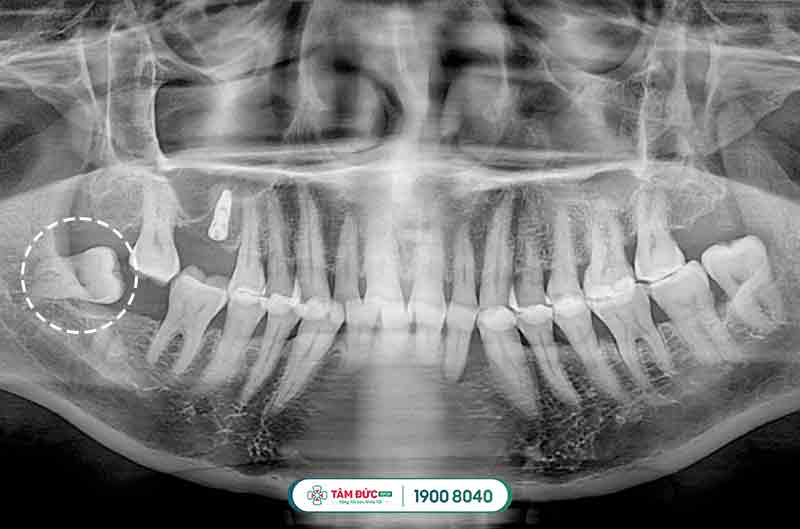

Đối với các trường hợp mọc răng khôn bị thiếu chỗ vì lúc này xương hàm đã ngừng tăng trưởng và phát triển, chịu tác động bởi quá trình ăn uống hàng ngày, khiến răng khôn bị mọc ngầm dưới nướu, mọc lệch đâm vào má, vào răng bên cạnh gây nên tình trạng đau răng khôn dữ dội, khó chịu và ảnh hưởng đến cấu trúc hàm mặt, sức khỏe răng miệng.

Răng khôn mọc ngầm thường có hiểu hiện làm nướu sưng tấy, viêm đỏ, khó há miệng. Vì xương hàm không có đủ vị trí nên nó sẽ đâm sang răng bên cạnh, nó sẽ làm chiếc răng khỏe mạnh kế bên dần bị tiêu hủy, lung lay có thể dẫn đến sâu, nặng hơn nó sẽ khiến chiếc răng này bị xô đẩy chèn ép và rụng đi gây mất răng. Răng khôn mọc lệch, ngầm thường gây ra những cơn đau răng khôn âm ỉ kéo dài trong khoản 2 tới 3 ngày.